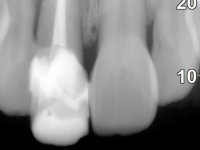

Female patient, 41 years old, non-smoker. It presented tooth 11 with a composite resin restoration, of great extension, very infiltrated and aesthetically poor. In the imaging exam, it was verified that the endodontic treatment was not technically satisfactory, but asymptomatic for almost 20 years. Between teeth 11 and 12 it showed a periodontal pocket certainly related to the non-adapted restoration. Tooth 11 showed a reduced mesiodistal diameter in relation to the symmetrical one. Medium thickness periodontal with satisfactory oral hygiene.

The treatment began with the placement of an intraradicular post and the creation of a new composite resin restoration. This procedure was performed with a surgical approach that allowed the remaining margins to be completely exposed, which were shown to be at a very infra-gingival level. Simultaneously, the periodontal pocket was curetted and root scaling and root planning of adjacent teeth were performed. Two months after this first intervention, the making of the crown began. A pre-print on silicone was performed to make a temporary crown with dual-cured composite resin. Gingival retraction was performed using the technique of kaolin paste compressed by the provisional crown. The impression was made using the double-mix technique with double viscosity with quick-setting silicone. In the laboratory, a crown with a ceramic-coated Zr infrastructure was made. The crown slightly overlapped tooth 12, allowing a dimensionally mimicry of the symmetrical tooth. Its fit was confirmed and approved by the patient; it was definitively cemented with resin-reinforced glass ionomer cement.